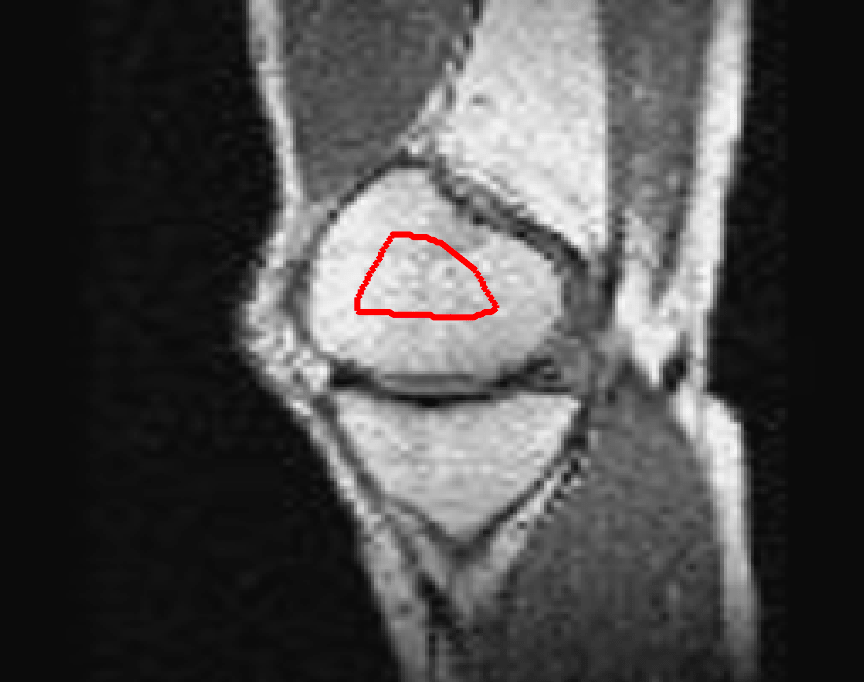

Test Images. We will perform initial tests on the images shown in Figs. 5–7. We have provided the ground truth and initialisation used for each image. Test Images 1–3 are synthetic, Test Image 4 is an MRI scan of a knee, Test Images 5–6 are abdominal CT scans, and Test Images 7–9 are lung CT scans. They have been selected to present challenges relevant to the discussion in §2. We focus on medical images as this is the application of most interest to our work. In the following we will discuss the results in terms of synthetic images (1–3) and real images (4–9). We also test the proposed approach on a larger data set of 30 CT images (a sample of which is presented in Fig. 18), comparing against existing selective methods detailed in §3.

Real Images. In Fig 12 we present results for Test Images 4–6. Here, the proposed model performs in a similar way to its competitors because these images are more typical selective segmentation problems in the sense that there is a clear distinction between the foreground and background intensities. In particular, the values in each case are: Test Image 4 , Test Image 5 , and Test Image 6 . It can be seen that the proposed model is competitive compared to previous approaches. The performance is quite poor for Test Image 5, but is arguably still the best for this challenging case. In Fig. 13 we present results for Test Images 7–9. Here the proposed model outperforms previous approaches significantly for each image. This is mainly due to the type of image considered. Specifically, the true intensities are: Test Image 7 , Test Image 8 , and Test Image 9 . The proposed model is capable of achieving results where , with other models failing completely in these cases.